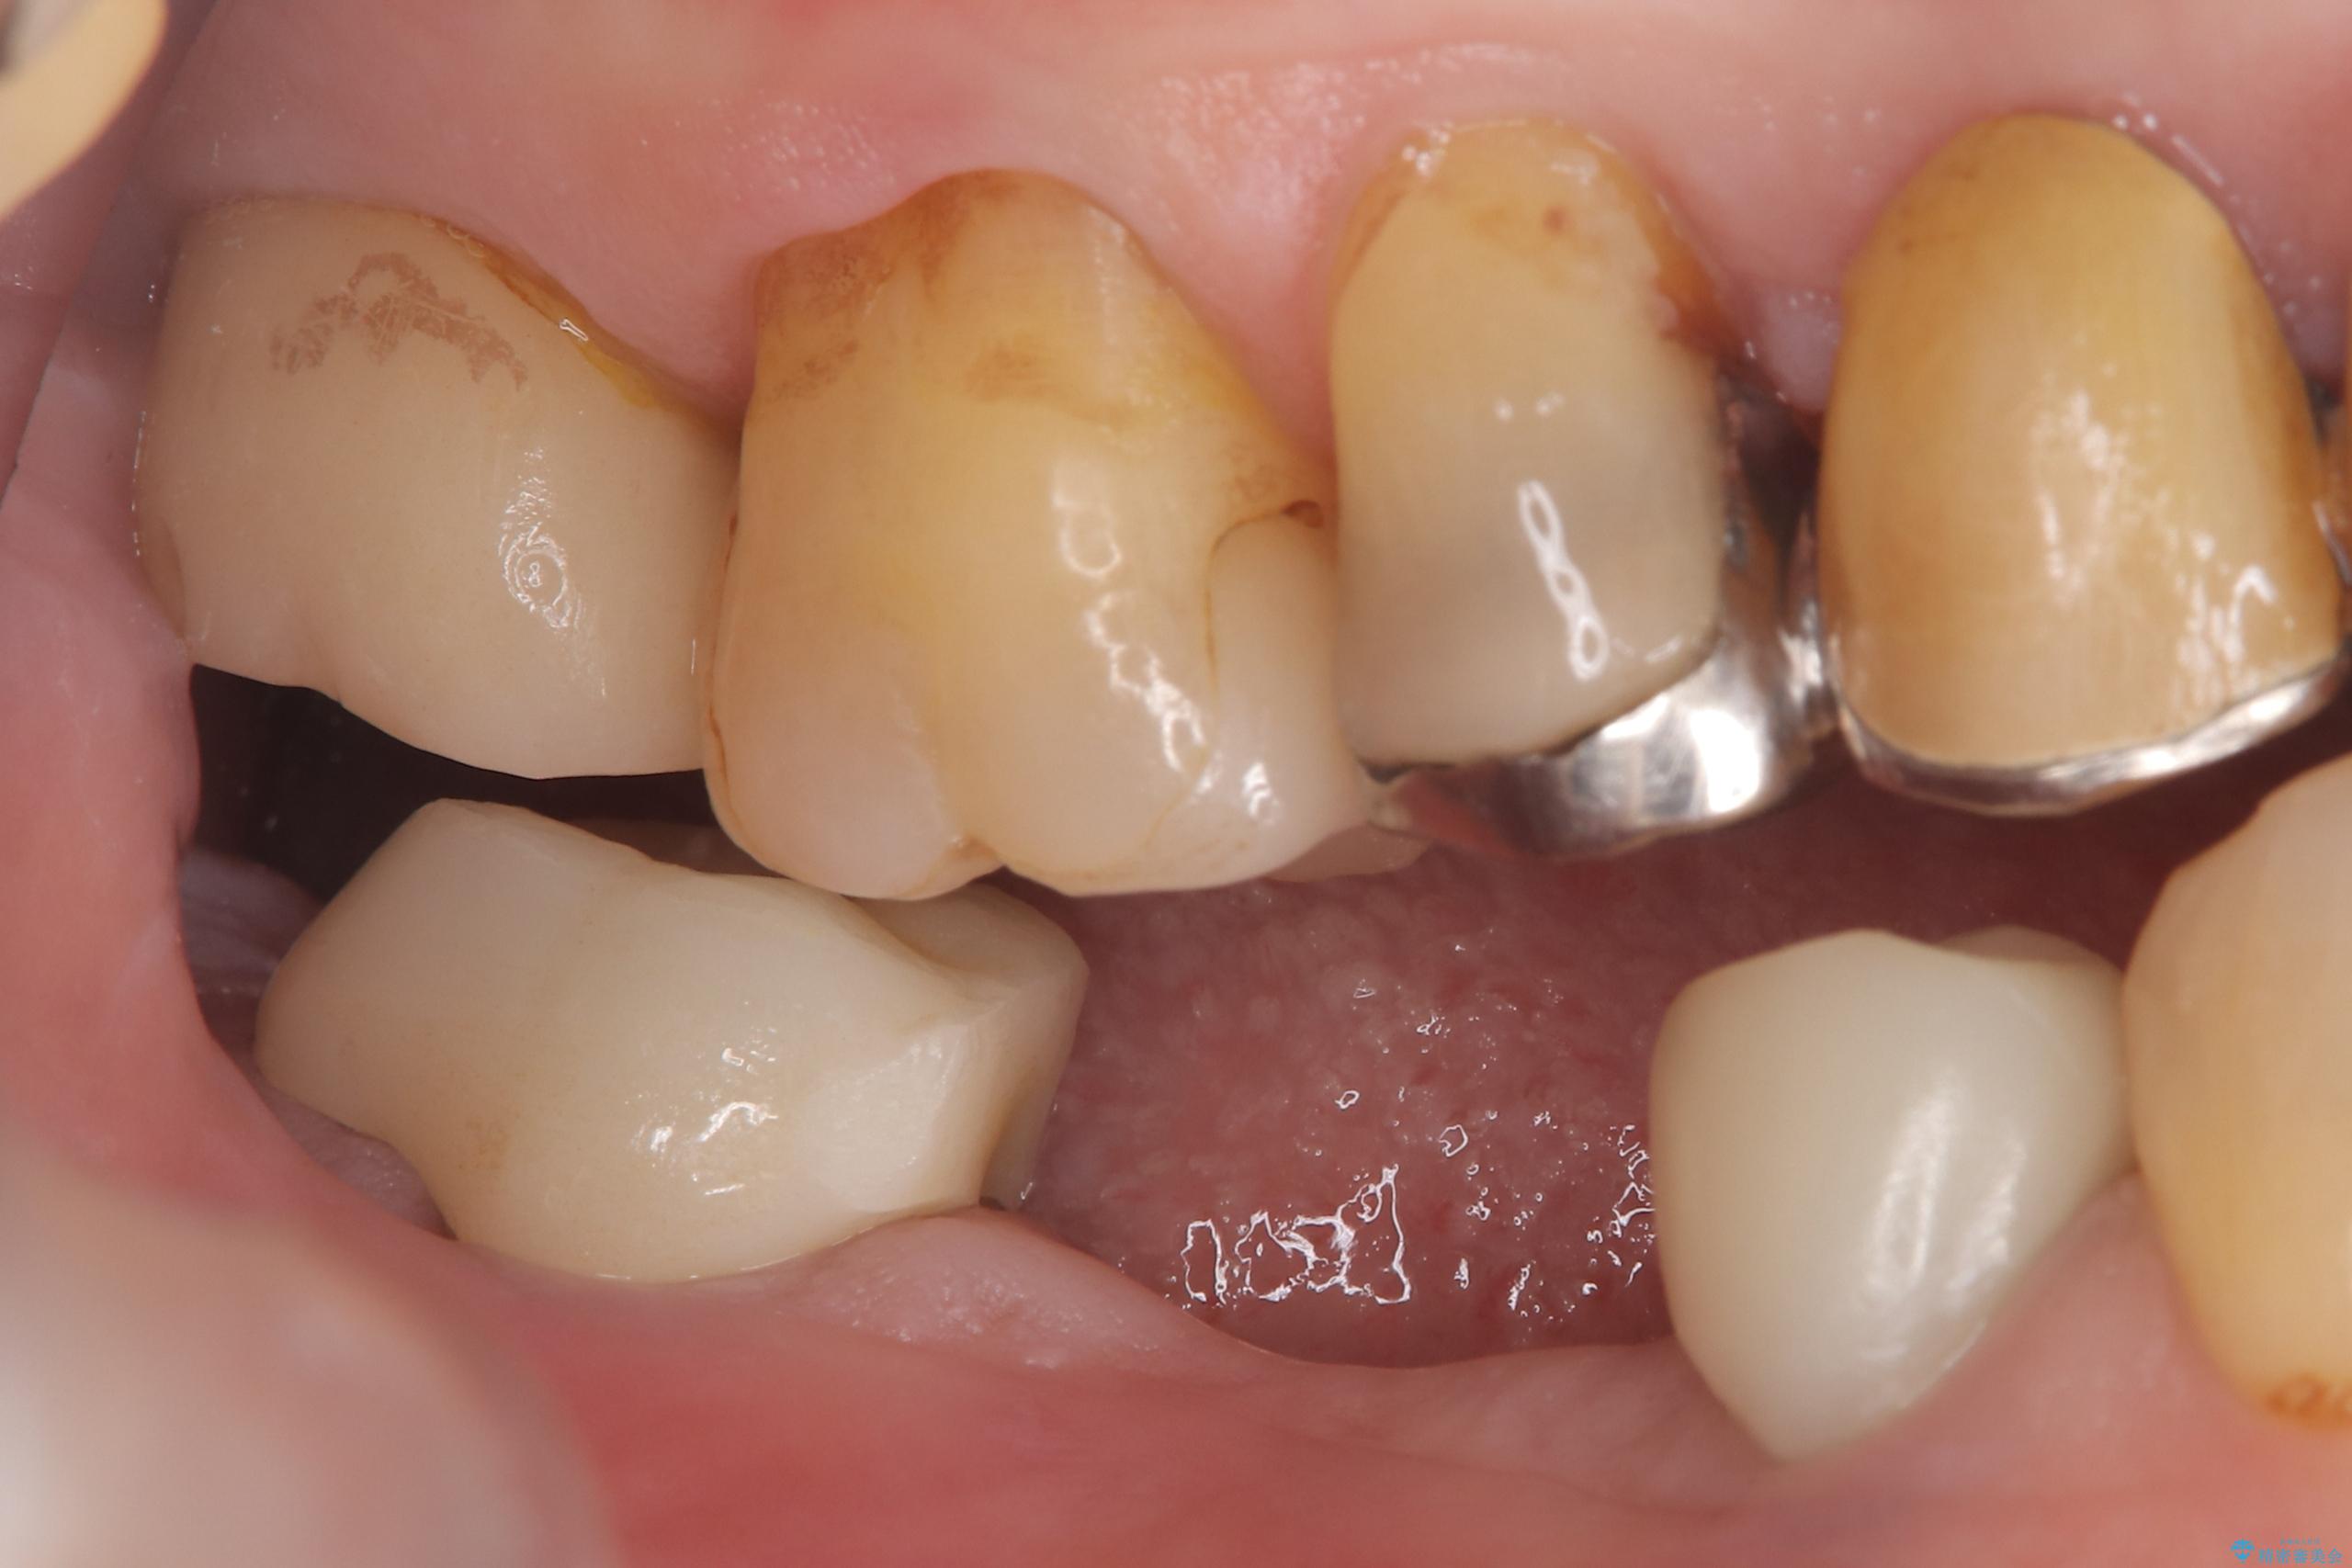

- 主訴:つい先日入れたセラミック(ジルコニア)ブリッジが奥歯部分で割れた。いつも同じ場所で壊れる。これで3度目。

セラミックに比べ、割れづらい金属(ゴールドでのブリッジのやり替えとなりました。

セラミックに比べ、破折リスクの少ない金属を使用したブリッジでのやり替えとなりました。

両支台歯が失活歯のため、どちらかもしくは両方の歯が破折した際、再度ブリッジを除去した治療が必要になるリスクとインプラント治療のご提案もさせていただきましたが、ブリッジでの治療を希望されました。

右下5番は支台歯CR築造を行っています。